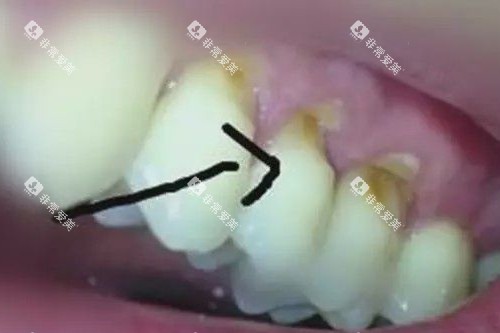

2.1 树脂补牙

国产树脂补牙:200元/颗起

3M-Z350进口树脂补牙:343元/颗起

美学树脂补牙(前牙修复):600元/颗起